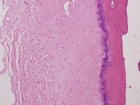

48 year old AAM with a two month history of a painful right shoulder and inability to reach overhead

Zoom image: Cell stain Cell stain.